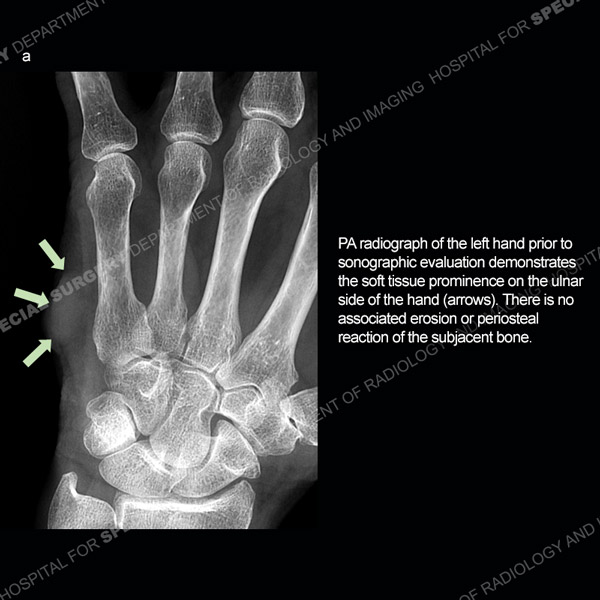

Featured Ultrasound of the Month CaseCase 186: 64-year-old woman with new left ring finger soft tissue swelling. |